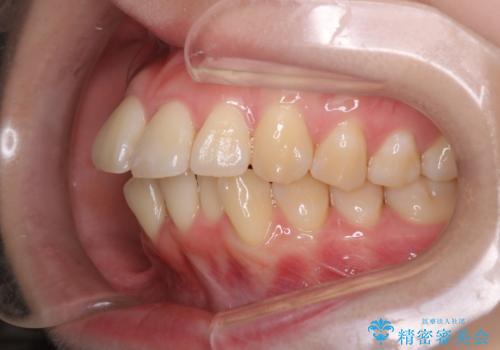

- 前歯が出ていることと、下の歯のがたがたで歯磨きがしにくいことを主訴に来院されました。

マウスピース矯正の希望があり、ワイヤーリカバリの可能性を伝えたうえでインビザライン抜歯矯正を行っています。

来院が途中途絶えたこともあり、4年ぐらい期間がかかりましたが、インビザラインだけで治療を終えることができました。